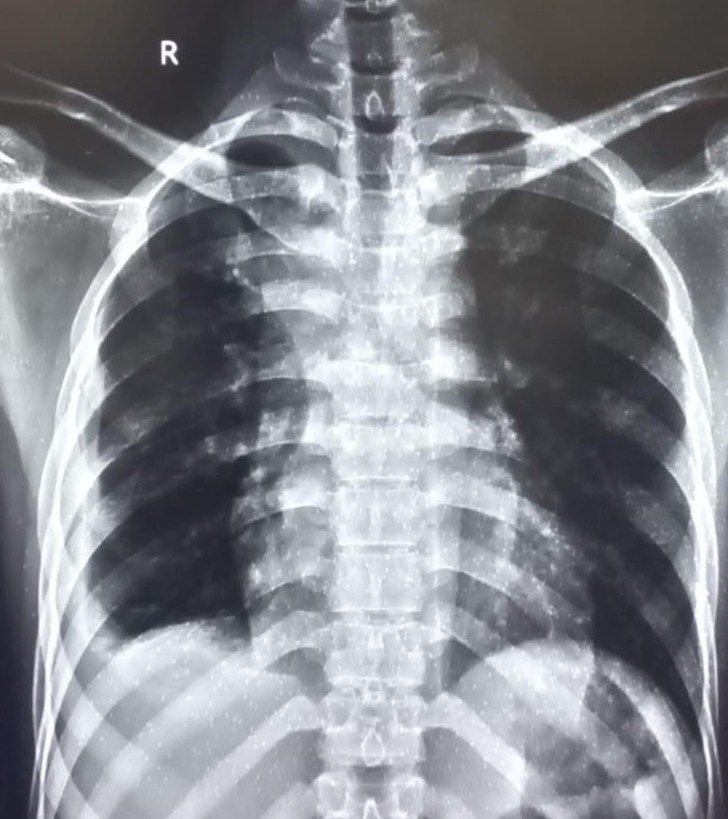

| 4422 | IGGMC, Nagpur, Nagpur | P2 | 29-50 | Vinod Mukardam | Consent taken on Paper | 35 Yrs. |

Provisional Diag : BREATHLESSNESS UNDER EVALUATION

Final Diag : Post TB sequalae (CxR- Bilateral Upper Zone Collapse With Pleural Effusion) |

Post TB Sequelae | Blunting of both lung costophrenic (CP) angles and a trachea shifted towards the right on a chest X-ray | Abnormality visible on x-ray |